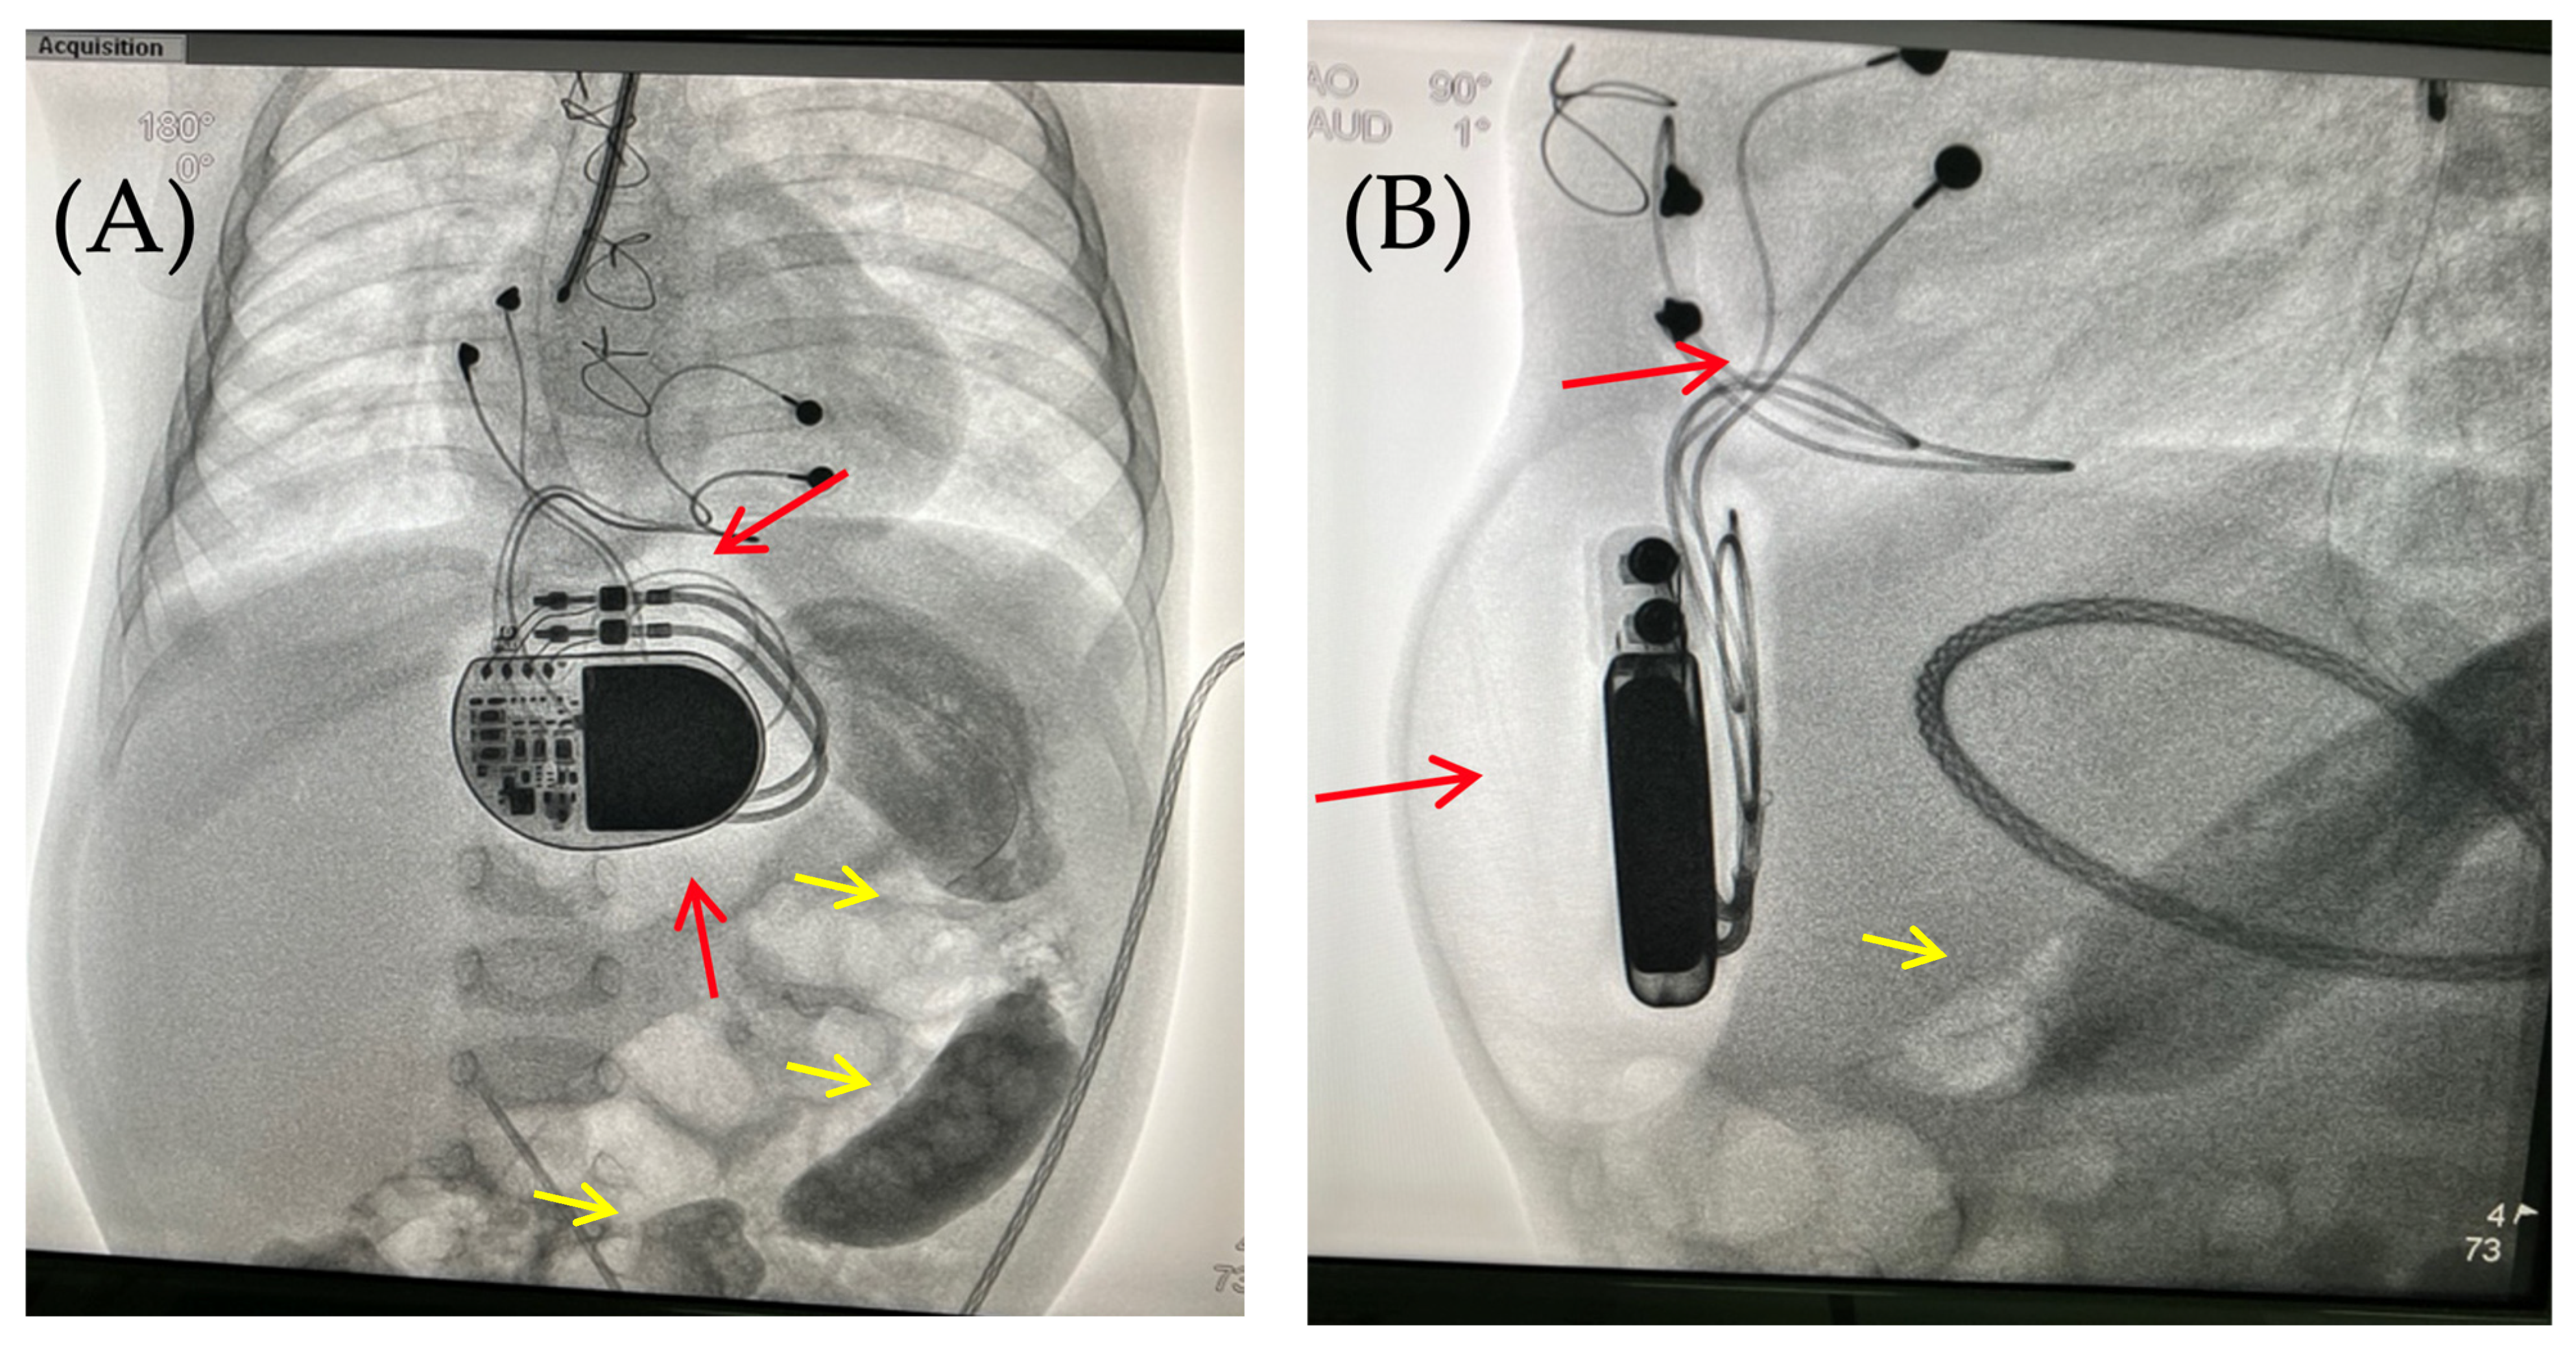

The skin in the area of the abdominal wall soft tissue bulge had normal color and temperature. Palpation revealed soft tissue with no detectable fluctuations. The pacemaker pocket was palpated within its bed. To rule out pneumothorax and perforation of a hollow abdominal organ, chest and abdominal radiography and fluoroscopy were performed, as well as GI contrast imaging (Figure 2 and Figure 3).

Fluoroscopy and chest and abdominal radiography revealed no signs of pneumothorax. A demarcated area of free air was visualized in the upper anterior abdominal wall along the midline, projecting to the pacemaker pocket. The passage of radiocontrast agent through the gastrointestinal tract was observed dynamically and found to be normal. No signs of hollow organ perforation or intestinal obstruction were detected (Figure 2, Figure 3 and Figure 4).

Figure 2. Chest X-ray—frontal (A) and lateral (B) view. Chest X-ray shows no pneumothorax, but pneumopericardium, pneumomediastinum and air in the pacemaker pocket site (red arrow) are present. One can also see the pacemaker electrodes (yellow arrow), the pulse generator (black asterisk), and the wire ligature (pink arrow). R: right side.